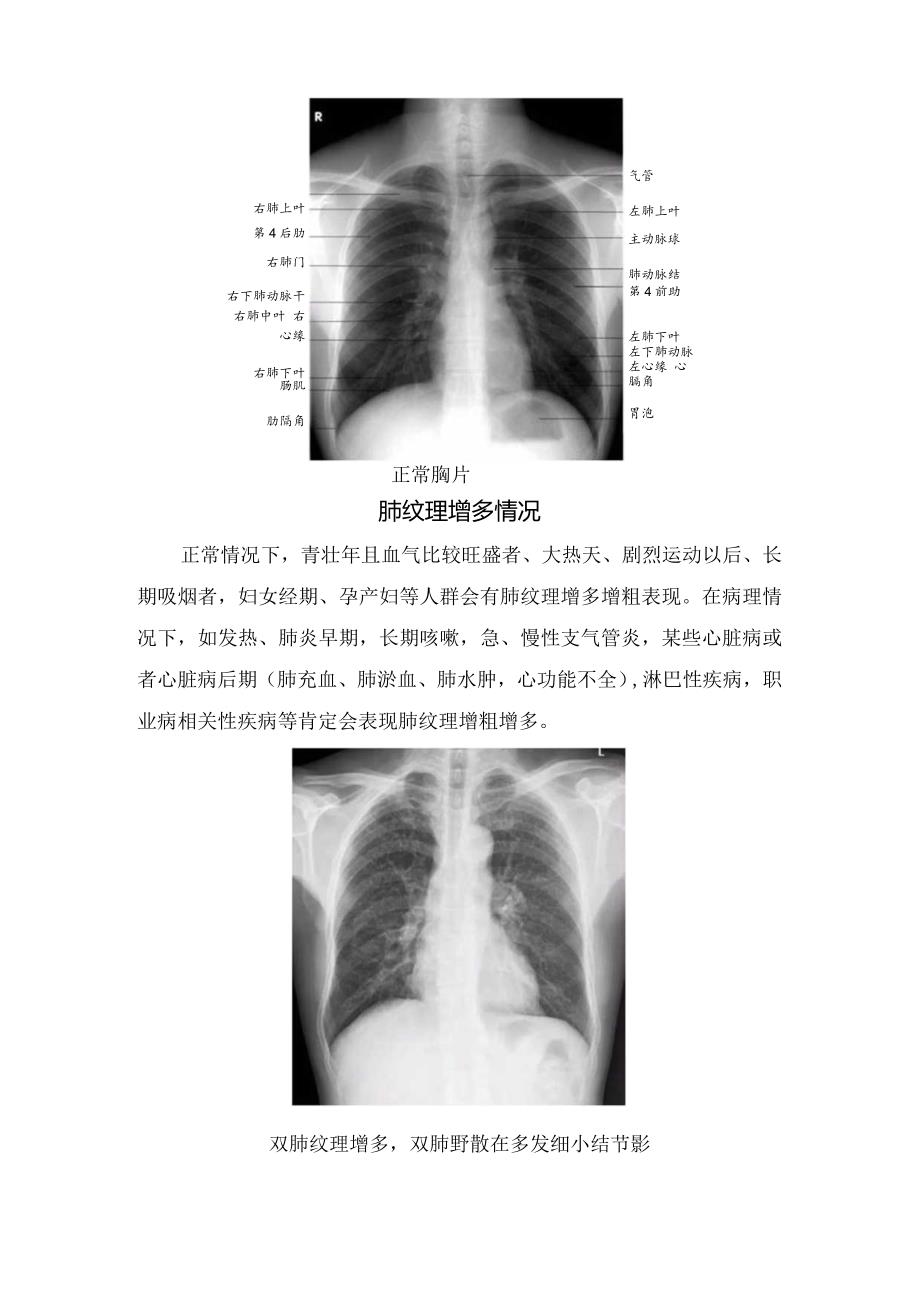

1、肺纹理构成、胸片表现、肺纹理增多情况及增多理解肺纹理构成自肺门向外呈放射状分布的树枝状影,称为肺纹理。肺纹理由肺动脉、肺静脉组成,其中主要是肺动脉分支,支气管、淋巴管及少量间质组织也参与肺纹理的组成。胸片上肺纹理在正位胸片上,肺纹理自肺门向肺野中、外带延伸,且逐级变细,至肺野外围几乎不能辨认。在正常时,下肺野纹理比上肺野多而粗,而右下肺野肺纹理比左下肺野多而粗。肺野的划分右肺上叶第4后肋右肺门右下肺动脉干 右肺中叶 右心缘右肺下叶 肠肌肋隔角正常胸片气管左肺上叶主动脉球肺动脉结第4前助左肺下叶左下肺动脉 左心缘 心膈角胃泡肺纹理增多情况正常情况下,青壮年且血气比较旺盛者、大热天、剧烈运动以后、

2、长期吸烟者,妇女经期、孕产妇等人群会有肺纹理增多增粗表现。在病理情况下,如发热、肺炎早期,长期咳嗽,急、慢性支气管炎,某些心脏病或者心脏病后期(肺充血、肺淤血、肺水肿,心功能不全),淋巴性疾病,职业病相关性疾病等肯定会表现肺纹理增粗增多。双肺纹理增多,双肺野散在多发细小结节影肺纹理增多理解某些设备因素,如在不同设备条件下所得到的照片或图像,会产生不同效果的肺纹理表现;同一病人在不同设备条件下也会产生不同效果的肺纹理表现。如普通摄影和数字化摄影效果就大不一样,后者由于分辨率高更能显示肺纹理结构;在主观判断上,不同放射科医生的阅历、水平、经验会有不同的判断标准;客观上不同工作场合的阅片条件、显示器的优劣影响判断效果。最后还得为了达成与临床医生之间的某种默契,作一些描述性诊断,以此消除病人的心理压力。肺纹理增多的意义,没有一个客观的、可以量化的标准,与被检者自身的健康状况、设备因素、诊断医生的个人经验有关。引起肺纹理增多的原因很多,既可以是病理性的,也可以是生理性或技术性的。一般来说,孤立地报告肺纹理增多,供临床参考价值不大。只有认真分析肺纹理增多的性质,并与其他X线表现和临床情况及技术条件结合起来综合考虑,才能得出正确的结论。也就是说,没有任何临床症状的肺纹理增多,完全可能是生理性的,即完全正常的。